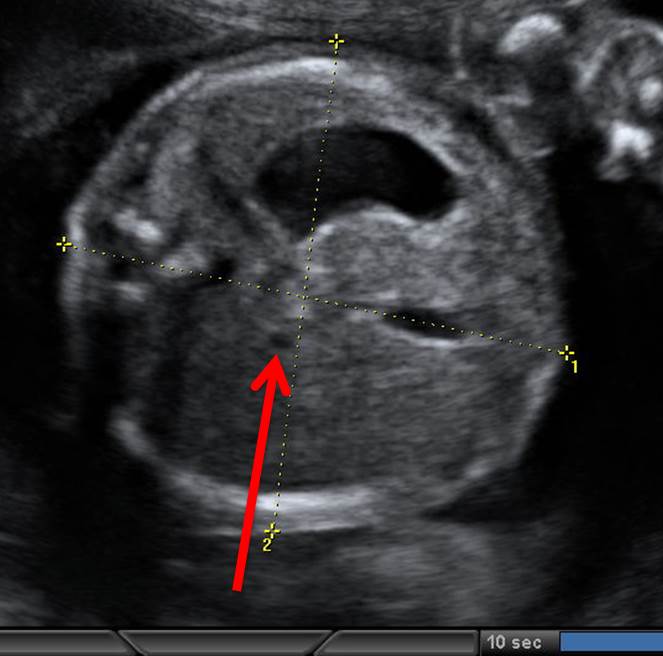

Вопрос 2

На какую структуру указывает стрелка?

• А — правое предсердие;​

• Б — левое предсердие;​

• В — правый желудочек;

• Г — левый желудочек

Ответ на вопрос 2